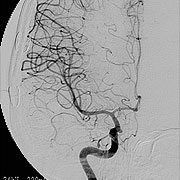

脳動静脈奇形

脳動静脈奇形は先天性の血管奇形のひとつで脳出血や痙攣発作の原因となります。最も基本的な治療法は手術による全摘出ですが、大きさ、発生場所等によっては放射線治療が選択される場合もあります。

当科では放射線治療班と症例検討を行い、個々の患者さんに最も適切は治療を提供しています。 脳動静脈奇形の手術では、術中脳血管撮影を常に行い、全摘出を確認しています。また場合によっては脳動脈瘤手術同様に電気生理学的モニタリングも併用し、確実、安全な手術を行っています(図7、8)。